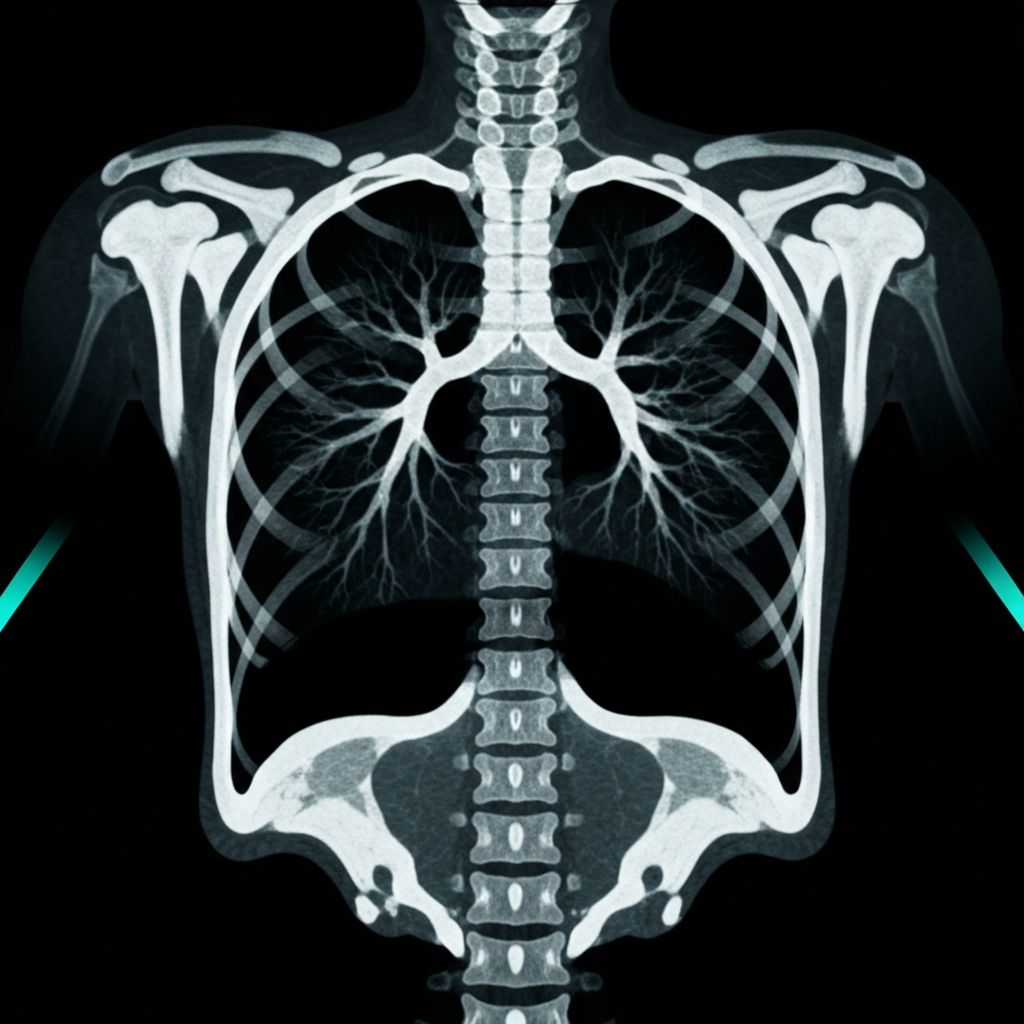

When you want human eyes.

Built by a patient who got tired of not knowing.

I spent $5k a year getting scans read. They'd call with a recommendation but couldn't wait 5 days for my blood test. I had to research biopsy risks myself. They never mentioned complications. Never mentioned alternatives. Never showed me a source.

So I built the tool I needed.

Join the waitlist for early access